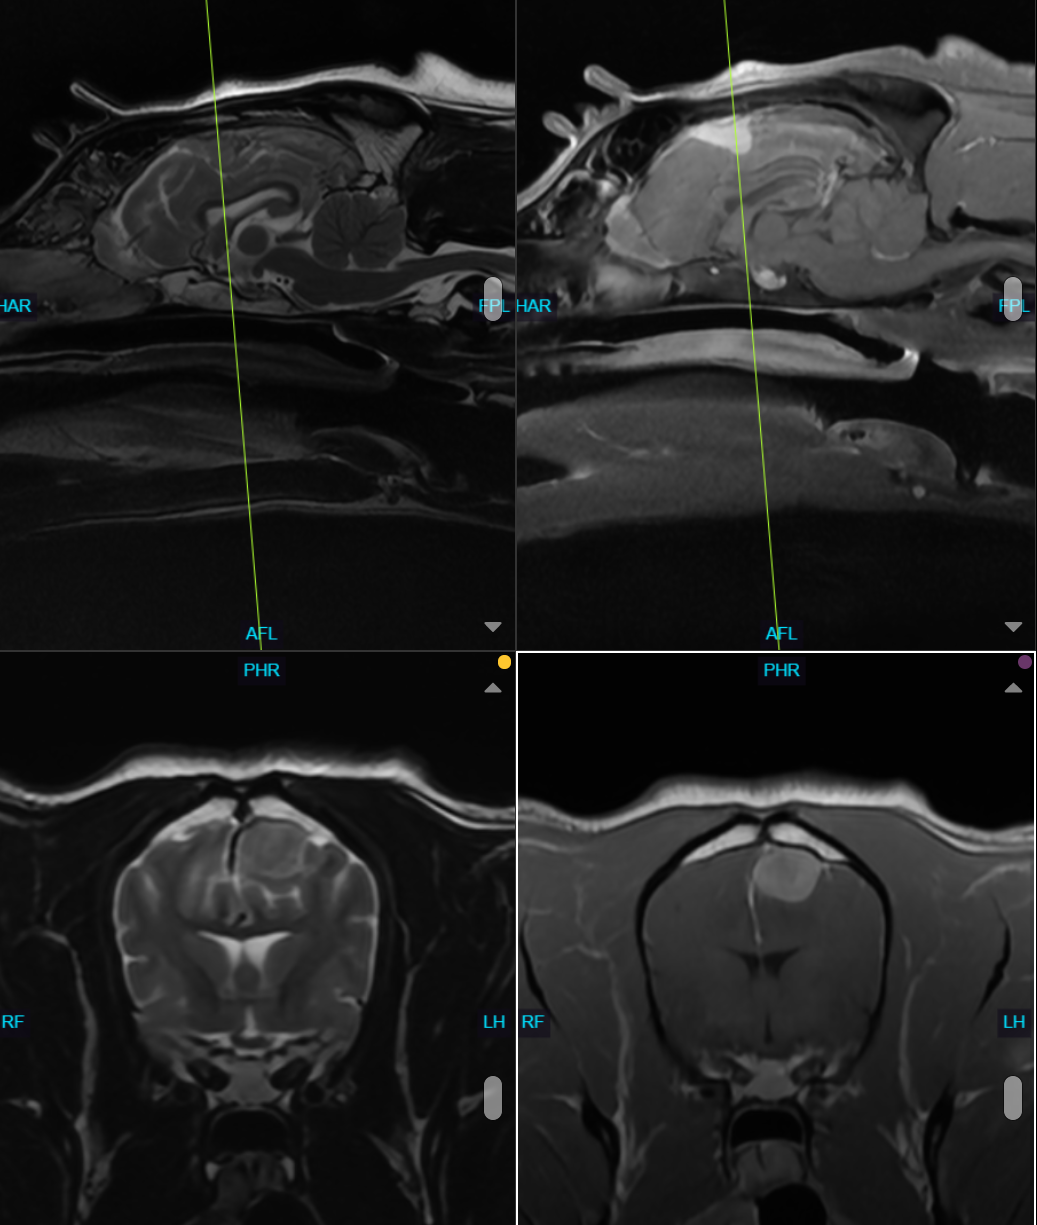

• Brain imaging (Magnetic Resonance Imaging (MRI) is the gold standard)

Diagnosing Brain Tumors in Dogs